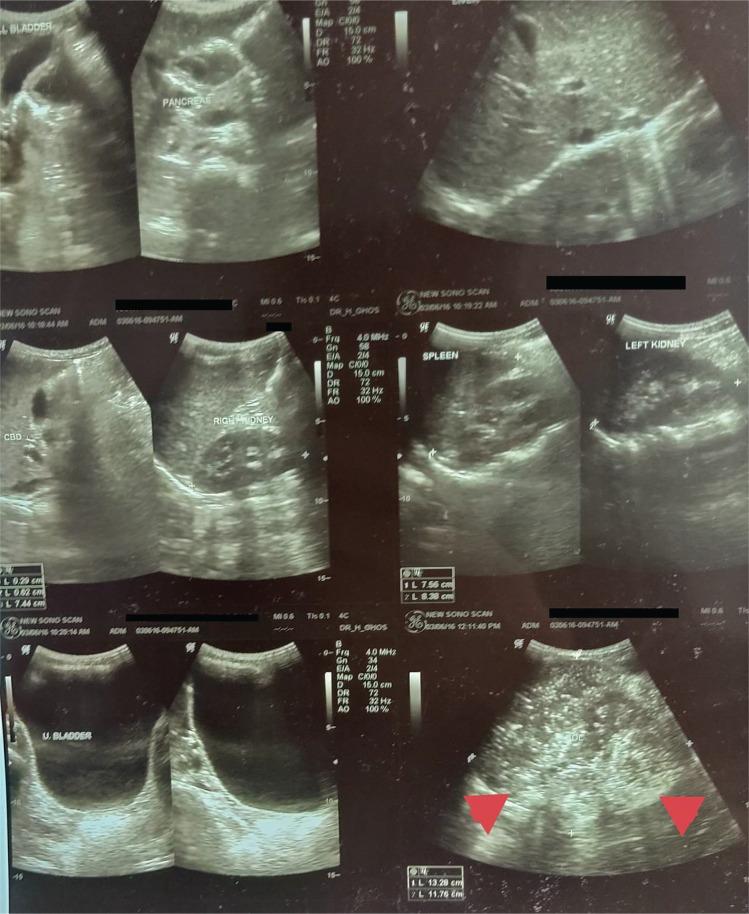

Complete gonadal dysgenesis with 46,XY karyotype is a clinical condition characterized by the absence of testicular tissue but with the presence of typical Müllerian structures in a phenotypically female individual. The condition presents as primary amenorrhoea or delayed puberty. Eventually, malignant neoplasms may arise. We report a case of a 16-year-old Indian male with Swyer syndrome presenting with primary amenorrhoea and with an earlier diagnosis of a malignant dysgerminoma in the right ovary.

完全型性腺发育不全伴 46,XY 核型是一种临床病症,其特征为表型女性个体中缺乏睾丸组织,但存在典型的 Müllerian 结构。该病症表现为原发性闭经或青春期延迟。最终,恶性肿瘤可能会发生。我们报告了一例 16 岁的印度男性患有 Swyer 综合征,表现为原发性闭经,并在右侧卵巢中较早诊断出恶性生殖细胞瘤。